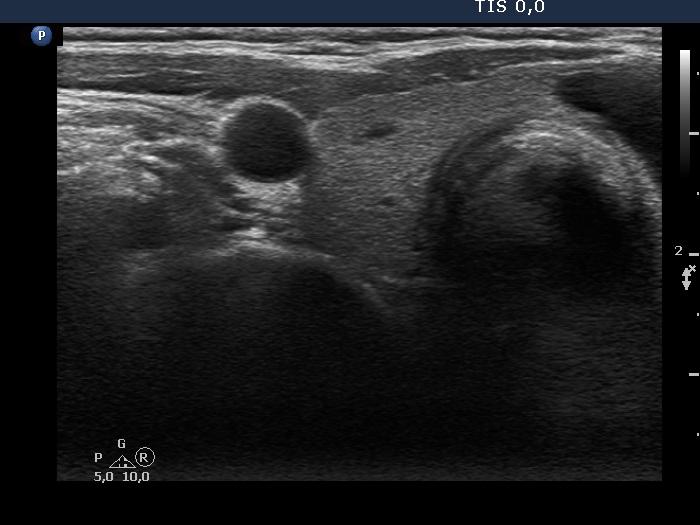

First examination (first row of images):

Clinical presentation: A 52-year-old woman was referred for ethanol sclerotherapy. Her cystic nodule was three times drawn off but recurred within weeks and caused compression signs. Cytology resulted in non-diagnostic, cystic degeneration.

Palpation: an elastic nodule in the isthmus.

Functional state: euthyroidism with TSH 1.76 mIU/L.

Ultrasonography. The thyroid was echonormal. There were several small cystic areas in the right lobe, while there was a large cyst in the isthmus. The latter lesion contained small, moderately hypoechogenic solid part which separated a small cystic area from the larger one. The solid portion contained smaller non-specific, and bit larger and brighter hyperechogenic granules. These are equivocal figures, the presence of microcalcifications cannot be excluded.

We told the patient that the possibility of a papillary carcinoma cannot be excluded on ultrasound presentation even if the cytology would be benign. Surgery was advised.

An isthmusectomy was performed. Histopathology disclosed benign hyperplastic nodule.